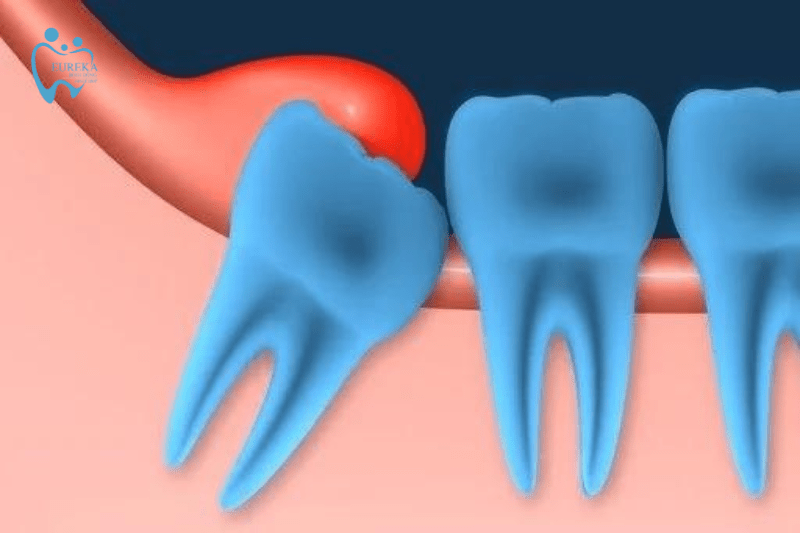

- Viêm lợi do hướng mọc răng khôn

Vì mọc sau cùng và vị trí trong cùng của hàm nên răng khôn không thể mọc đúng hướng như những răng khác. Chúng sẽ mọc nghiêng, ngang, đâm vào răng số 7, thậm chí là mọc ngầm dưới lợi. Từ đó khiến cho phần nướu bị sưng lên và khó được làm sạch, tạo điều kiện cho vi khuẩn phát triển. Lúc này lợi sẽ bị nhiễm trùng, đau nhức và trùm lên răng khôn.